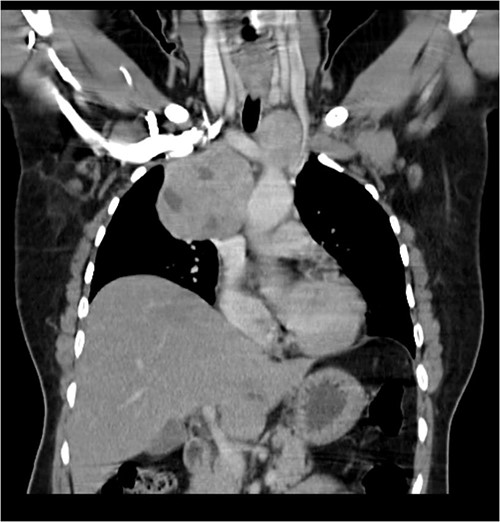

A 57-year-old female came with chest discomfort and cough since 1 month. The chest X-ray (Fig. 1) showed mass in the superior mediastinum. CECT thorax (Fig. 2) revealed the soft tissue density 7 cm × 7 cm (Fig. 3) in superior mediastinum abutting subclavian artery, azygous vein, anteriorly displacing superior venacava, anteromedially abutting arch of aorta, posteromedially compressing trachea and abutting right main bronchus. A 4.9 cm × 5 cm mass in the left side superior mediatinum was seen abutting internal jugular vein and brachiocephalic artery. USG showed the presence of normal thyroid in the neck. CT guided biopsy from the right mass showed ectopic thyroid tissue (ETT)-colloid goiter. Due to close proximity with major vessels sternotomy done. Mass in the left side 5 cm × 5 cm (Fig. 4) in the superior mediastinum was identified, on dissecting superiorly, which was free from the thyroid in the neck and abutting the IJV, brachiocephalic artery and left innominate vein that were separated with meticulous dissection.

CECT scan showing the right side mass displacing superior nn(SVC).